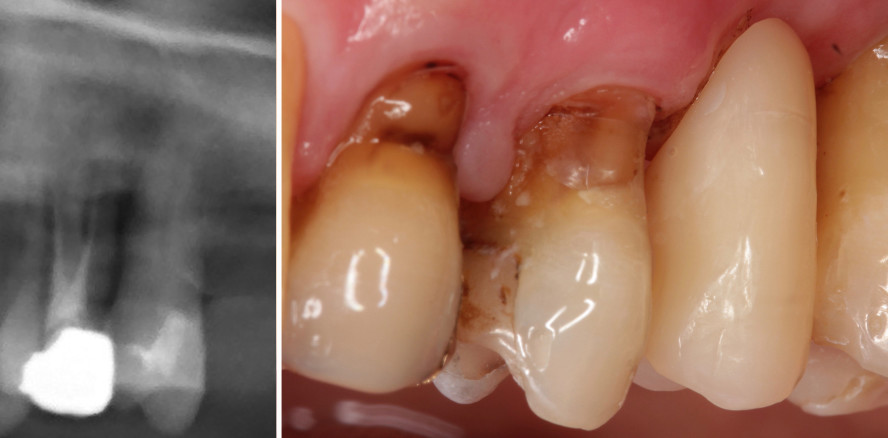

Ist trotz Initialtherapie und regelmäßiger UPT keine Verbesserung der Parodontitis zu erzielen, steht sowohl der Behandler als auch der Patient vor einem Problem. Die Prognose und Wertigkeit der Zähne ist nicht ausreichend genug, um diese für eine Zahnersatzversorgung zu nutzen. In diesen Situationen können Langzeitprovisorien eine Lösung sein. Durch neue, moderne Möglichkeiten, Versorgungen zu fräsen und in Zukunft auch durch 3-D-Drucker herzustellen, kann schnell und kostengünstig Zahnersatz angefertigt werden. Marylandartige Brücken sind in diesen speziellen Fällen vorteilhaft. Dies ist eine festsitzend eingeklebte Versorgung, welche jederzeit ausgetauscht werden kann (Abb. 3d). Ein umfangreiches Beschleifen von prognostisch ungünstigen Zähnen entfällt. Gerade Zähne mit höheren Lockerungsgraden können so stabilisiert werden. Im Falle einer Überbelastung löst sich der Klebeverbund. Im gezeigten Fall ist trotz regelmäßiger Parodontaltherapie keine Besserung zu erreichen (Abb. 3a und b). Nach Fraktur und notwendiger Entfernung von Zahn 26 wurde dieser durch ein gefrästes marylandartiges Langzeitprovisorium ersetzt (Abb. 3c bis f). An eine definitve Brückenversorgung ist aufgrund der Prognose der Zähne nicht zu denken. Der Ersatz durch ein Implantat aufgrund der nicht entzündungsfreien Nachbarzähne ist nicht zu empfehlen. Da die Parodontaltherapie nicht anschlägt, ist von implantologischen Eingriffen insgesamt abzuraten.